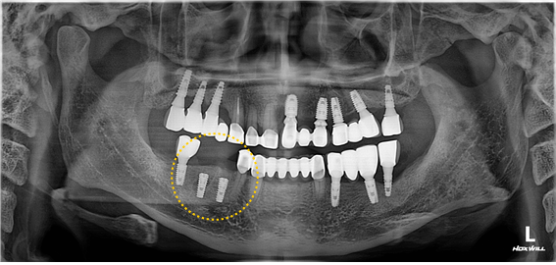

심하게 썩은 치아를 발치하고, 가성비가 좋은 덴티스 임플란트를 식립 및 뼈이식을 하였습니다.